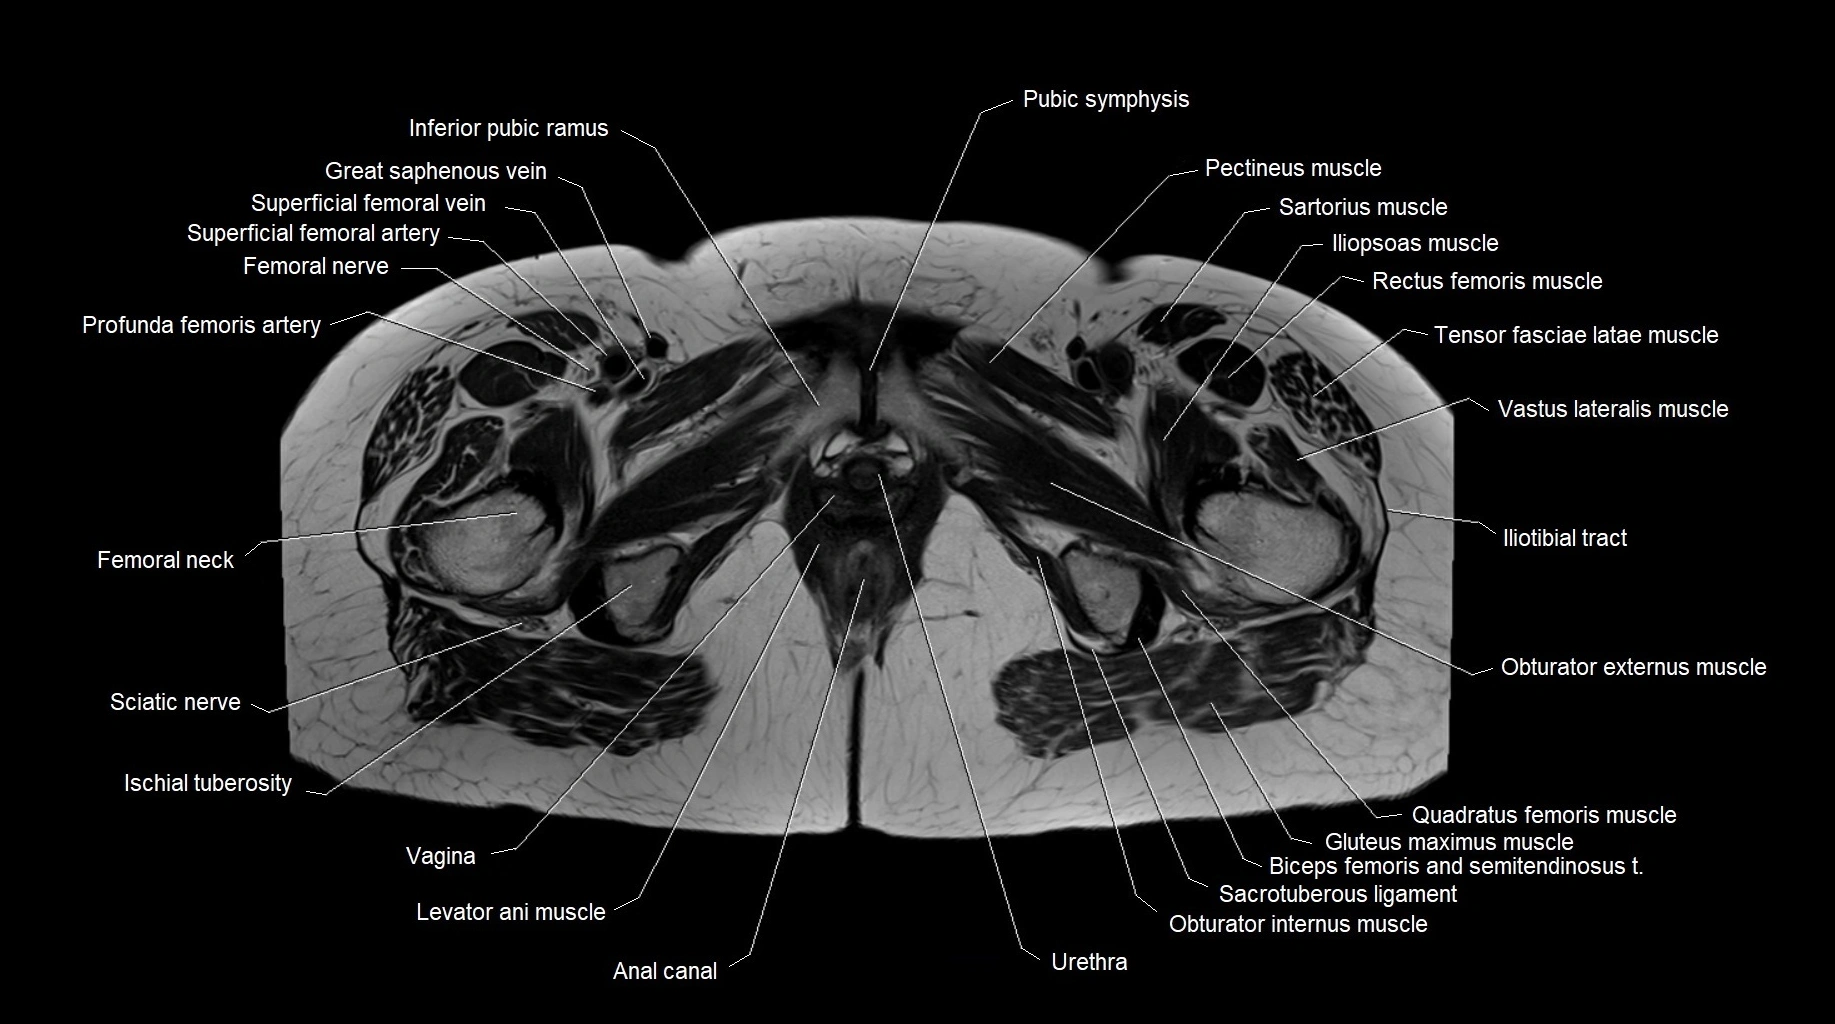

- Anal canal

- Levator ani muscle

- Obturator externus muscle

- Obturator internus muscle

- Pectineus muscle

- Quadratus femoris muscle

- Sacrotuberous ligament

- Sartorius muscle

- Sciatic nerve

- Vagina